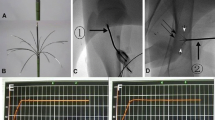

Nine rabbits were divided into three groups for femoral ablation, exposing the growth plate to different temperatures (T1 = 43–45 °C; T2 = 46–48 °C; T3 = 49–51 °C). After 5 weeks, the changes in the femurs were assessed by macroscopic images, micro-CT, haematoxylin and eosin staining, and immunohistochemistry of Col2a1 (type II collagen). At the cellular level, rabbit epiphyseal chondrocytes were exposed to 37 °C, 44 °C, 47 °C and 50 °C for 5 min. Then, proliferation and chondrogenic differentiation were detected.

The rabbits in the T2 and T3 groups developed length discrepancies and axial deviations of femurs, abnormal newly formed bone in the marrow cavity, disorganized growth plates and decreased Col2a1 expression. At the cellular level, the cells exposed to 47 °C and 50 °C for 5 min showed decreased viability, increased apoptosis, decreased extracellular matrix synthesis and decreased matrix mineralization. However, the changes in rabbits in the T1 group and cells at 44 °C did not show a significant difference.